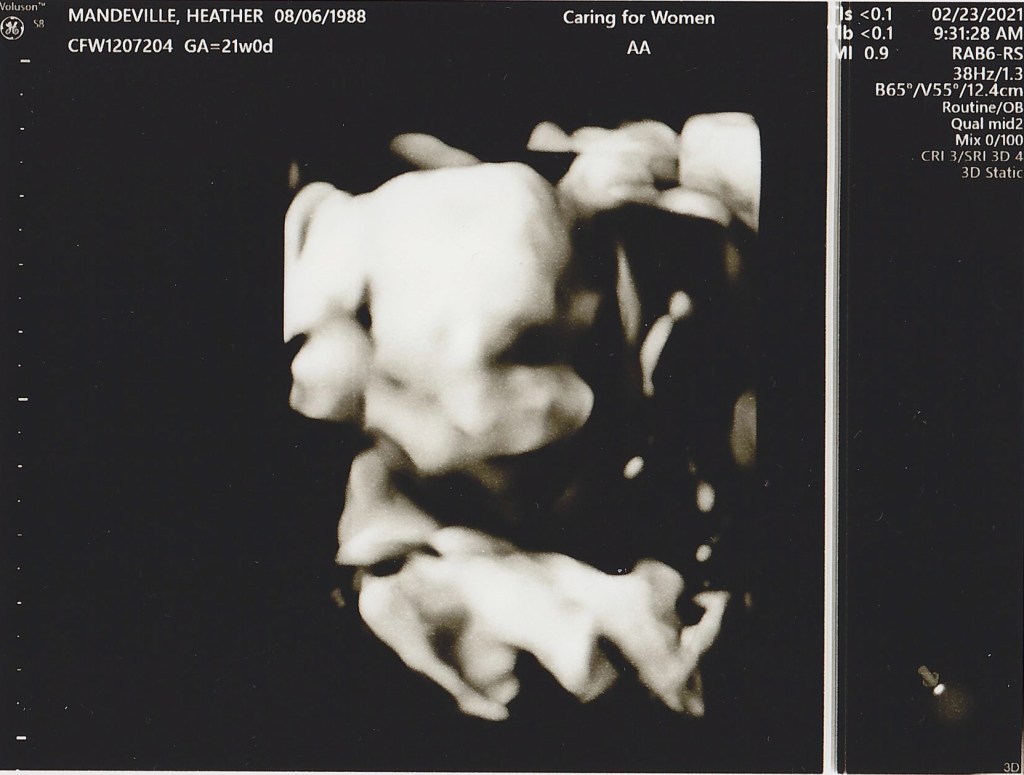

20 week sonogram

IT’S A BOY!! We found out today we are having a boy and we could not be more excited! Everything is looking good, Heather and the baby are healthy and he is progressing as expected. Now we get to start really planning to welcome him into this world, so many things to do in the next 20 weeks!